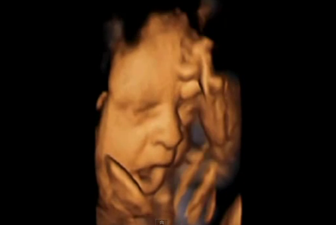

The Most Amazing Piece Of Research: 4D Scan Shows Babies Yawning In The Womb